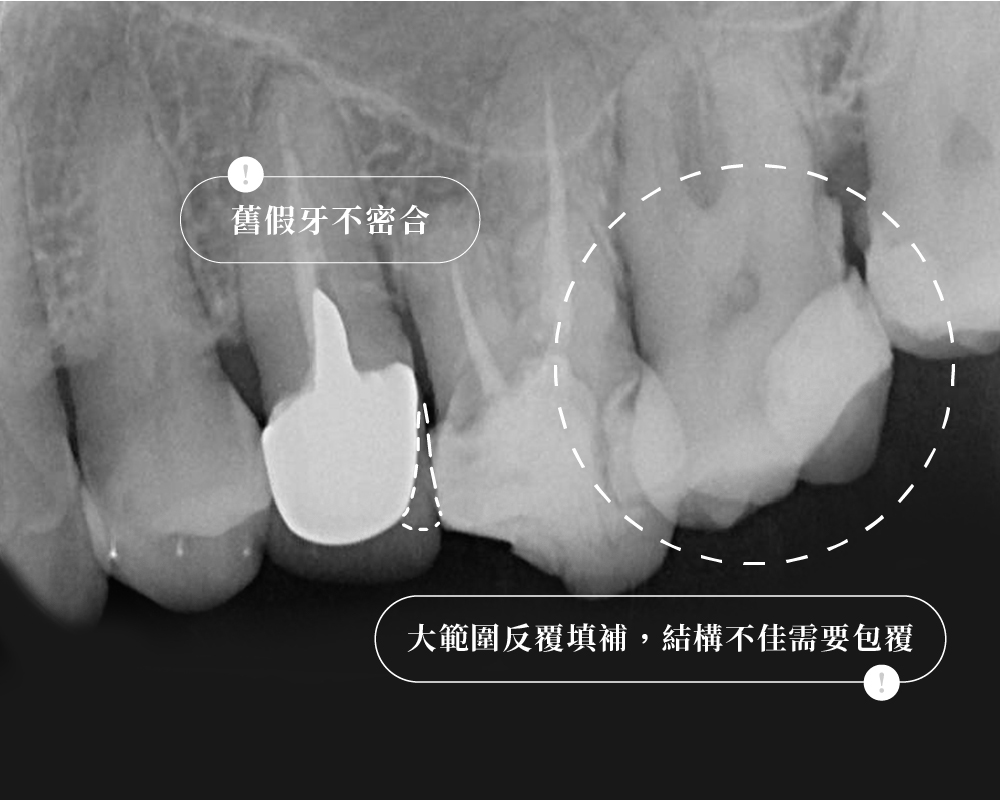

2. 鄰牙本身健不健康,決定了這座「橋」該不該搭

很多人會把焦點放在「中間少了一顆牙」,

但臨床上真正需要一起評估的,往往是缺牙兩側的鄰牙狀況。

牙橋有點像搭橋:中間缺牙的位置是橋面,前後兩顆牙則像橋墩。

橋墩本來就老舊、破損需要補強,把它們一起納入設計,未必是壞事

但如果兩個橋墩本來都穩穩當當、結構完整,卻為了補中間一塊空缺,反而把兩側也削掉一部分來搭橋,那這個代價就要更仔細思考。

所以在評估牙橋時,我不會只看「缺了哪一顆」,而是會進一步看:

前後兩顆牙,是本來就需要保護,還是本來就值得盡量保留?

簡單來說,牙橋不是不能做,關鍵在於前後兩顆牙值不值得一起被納入設計。